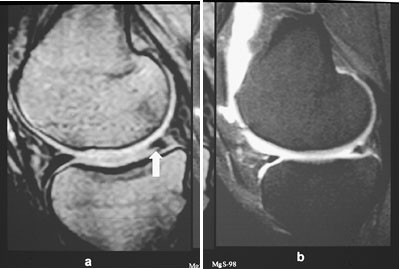

Ved kroniske knesmerter kan man med MR påvise eventulle osteonekroser med ledsagende margødem lenge før forandringene er synlige ved konvensjonell røntgenundersøkelse, og man kan som oftest også si noe om hvorvidt forandringene er potensielt reversible eller irreversible. Ved tidlig osteonekrose vil det være et subkondralt område på vektbærende del av aktuelle kondyl med nedsatt signal på T1-vektet sekvens. Gradientekkosekvenser er spesielt velegnet. Dette er ledsaget av margødem, som viser økt signal på STIR-sekvensen. Hvis det i tillegg kan påvises et subkondralt avstøtt fragment på mer enn 14 ⋅ 4 mm, er forandringen potensielt irreversibel.

MR-undersøkelse av bekken og hofter blir ofte utført hos pasienter med hoftesmerter hvor konvensjonell røntgen er negativ. MR kan tidlig påvise en osteonekrose og stadieinndele den (fig 13). En klinisk tilstand kjent som beinmargsødem i forbigående osteoporose gir intraktable smerter (10). Dette er en tilstand hvor det er lokalisert osteoporose i caput/collum femoris assosiert med økt væske mellom trabeklene. Røntgenbilder er som oftest normale, spesielt tidlig i forløpet. MR vil vise generelt nedsatt signal på T1-vektet sekvens og betydelig økt signal på STIR-sekvens (fig 14). Tilstanden sees oftest hos middelaldrende menn. Den vedvarer i opptil seks måneder. Årsaken er ukjent.